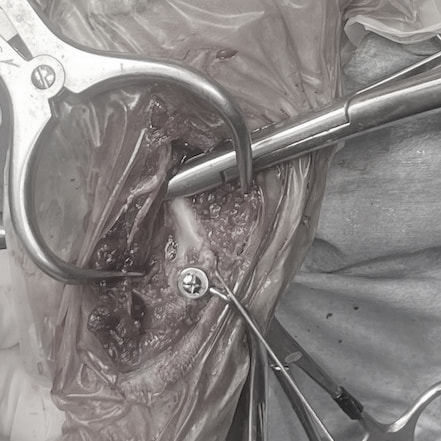

症例3:キルシュナーワイヤーのピンニングによる整復

ペルシャ猫 11ヶ月齢 雄

他院にて左大腿骨遠位の成長板骨折(salter-harrisⅠ型)が認められており、治療相談を目的として来院。当院にて、キルシュナーワイヤーを用いたピンニングにより骨折部位の整復を行いました。術後の経過は良好で、現在も経過観察中です。

Arthrex社のターゲティングデバイスを用いてピンニングの位置を調整することで、確実な固定を行っています。当院ではこの手術器具以外にも、人の手術にも使用される様々な器具を導入し、手術精度を高め、また医療メーカーと新しい器具の開発、試作にも取り組んでおります。